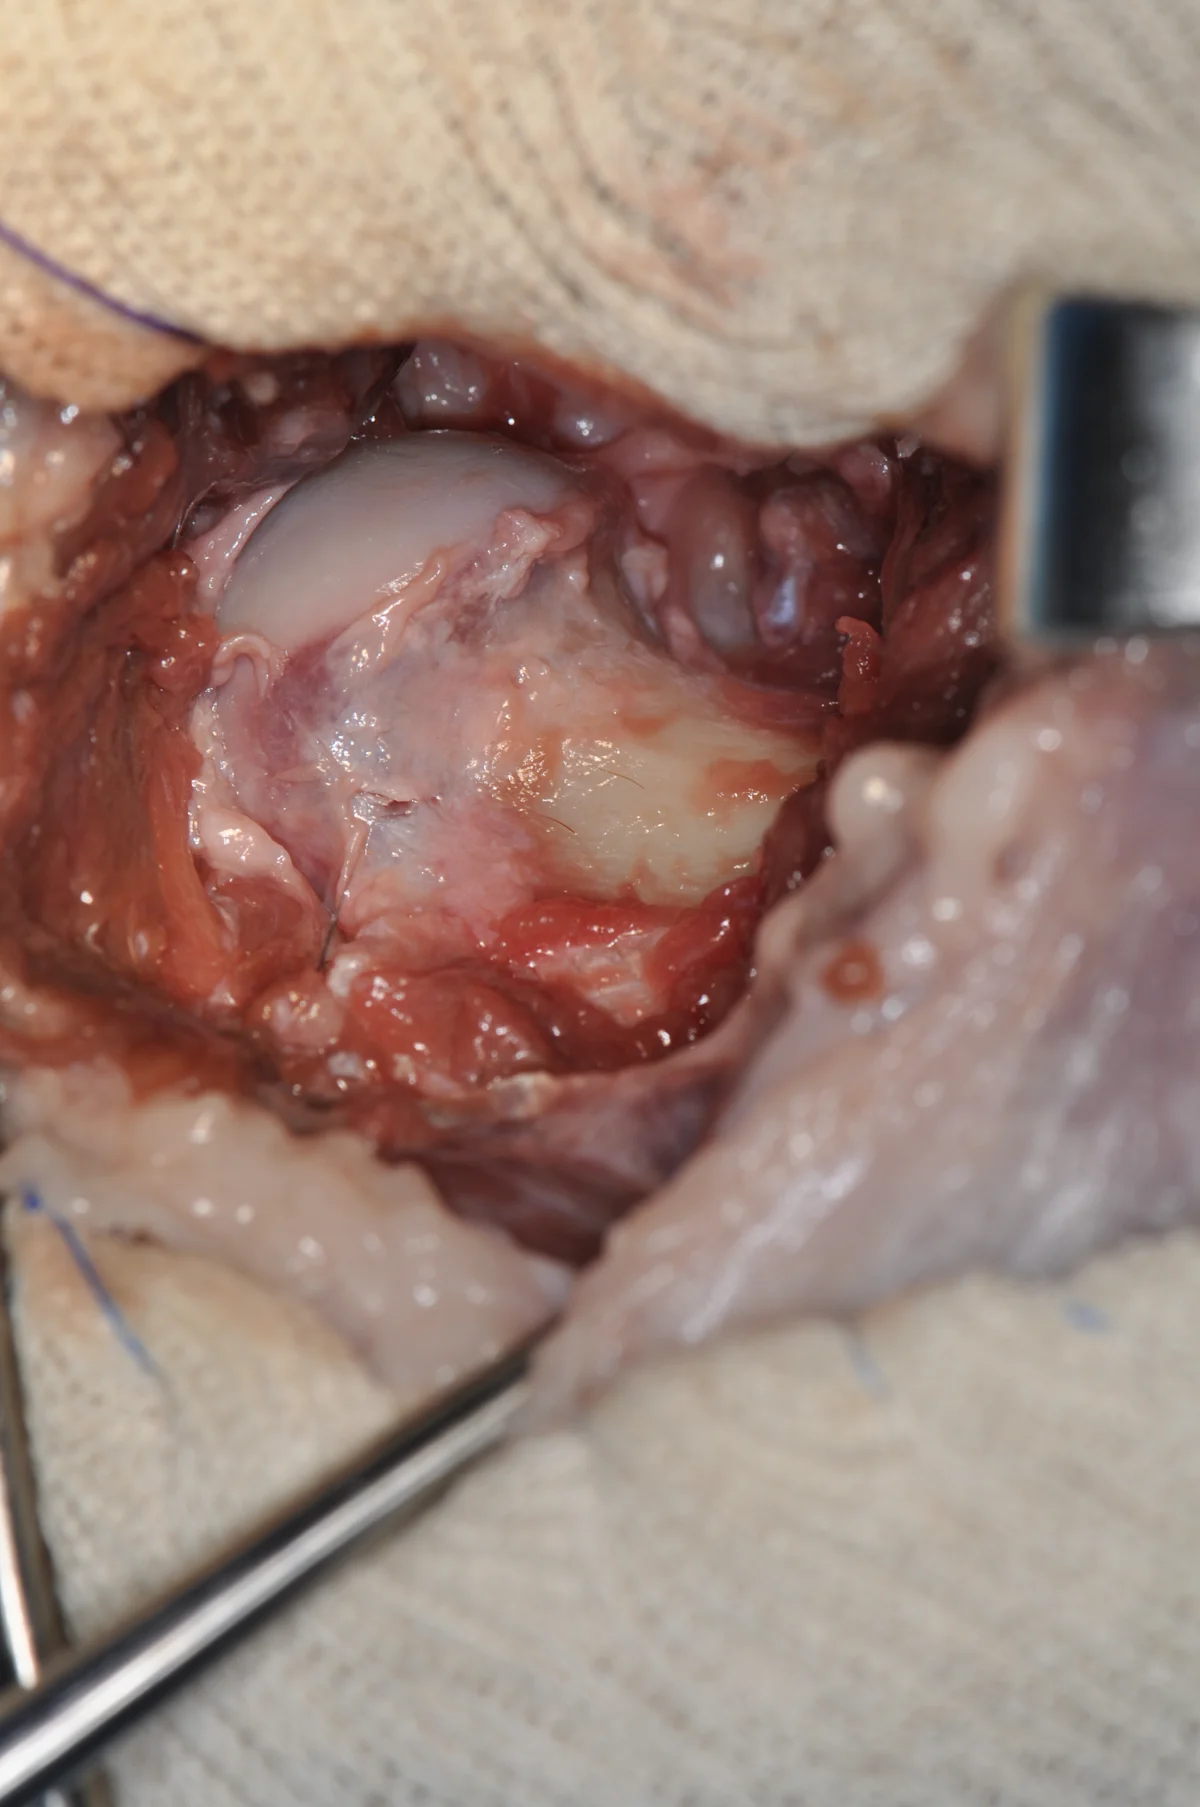

Once the cut is completed, the tissue to be removed is grasped with a bone-holding forcep. The femur is then carefully palpated for residual bony prominences or irregularities. The hip is placed through a thorough range of motion. Any “grinding” or bony contact between the femur and hip should not be ignored.

At this point, the use of rongeurs or a rasp can be used to excise remaining tissue and to smooth rough surfaces (A). Inspection of the resected femoral head and neck can give some insight as to whether additional tissue needs to be excised (B).